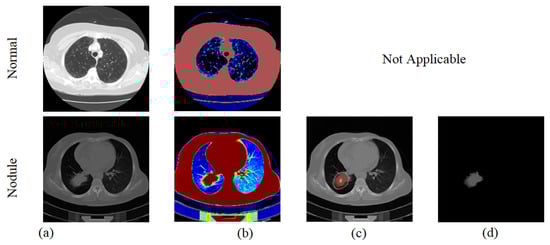

3.2. Nodule Segmentation

3.3. Nodule Classification